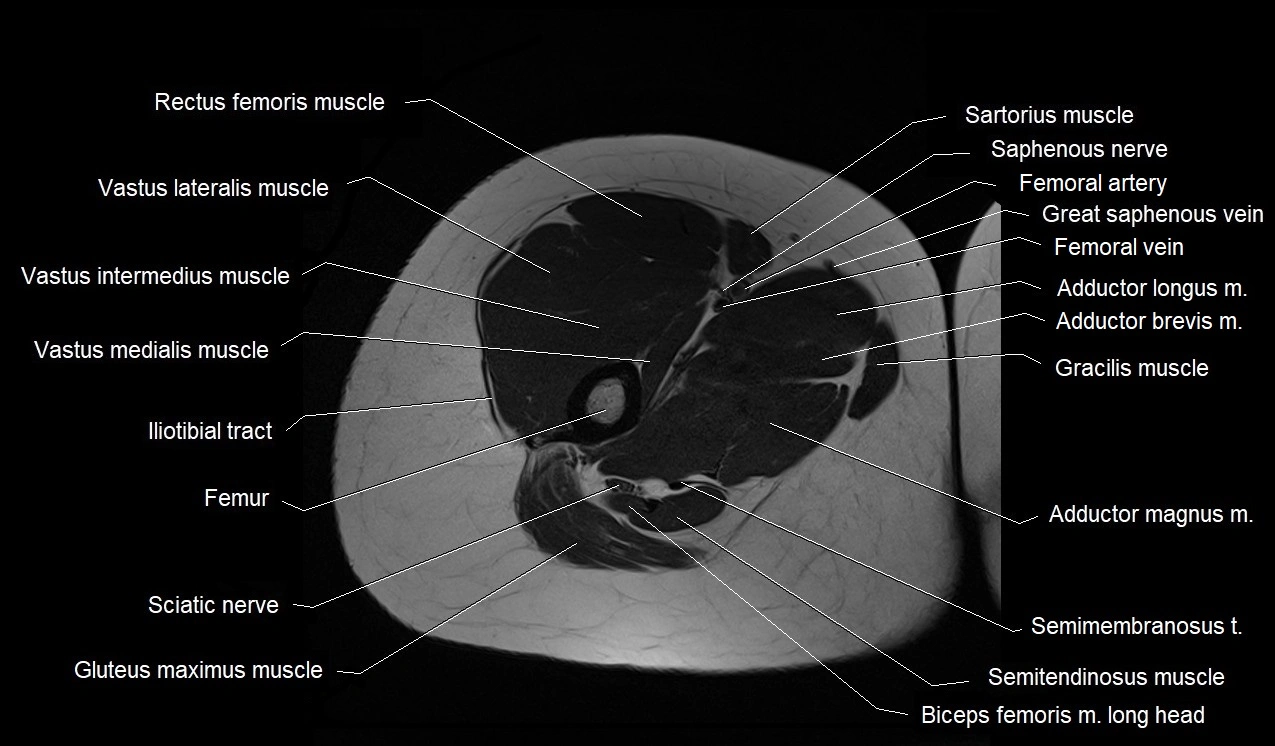

- Femoral artery

- Femoral vein

- Gluteus maximus muscle

- Gracilis muscle

- Iliotibial tract

- Obturator externus muscle

- Obturator internus muscle

- Rectus femoris muscle

- Sartorius muscle

- Semimembranosus muscle

- Semitendinosus muscle

- Vastus intermedius muscle

- Vastus lateralis muscle

- Vastus medialis muscle